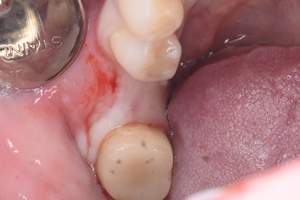

口腔内写真

- Befor

- After

| 年齢 | 50代・男性 |

| 主訴 | 部位:左下6番7番 主訴:左下奥歯腫れて痛い。 |

| 治療内容 | 左下6番抜歯、左下6番7番骨造成、インプラント埋入 |

| 治療費 | 合計:1,232,000円 ・内訳 診断料:55,000円 サージカルガイド2本:66,000円 GBR:110,000円×2本 埋入料:165,000円×2本 静脈内鎮静麻酔:77,000円 2次OPE:22,000円×2本 仮歯:55,000円×2本 上部構造(フルジルコニア):165,000円×2本 (2023年1月現在) |

| 治療期間 | 約8ヶ月 |

| 治療方針 | 元々支台歯に負荷がかかりやすいとされている延長ブリッジを抜歯し、1本単体でしっかりかめるようにインプラントを2本埋入した。骨吸収も進んでいたため、※GBR法で骨造成を同時に行った。 治療と並行して、全顎的な歯周病治療も行い、今後は歯周病が進行しないよう、こまめにメンテナンスに通っていただく。 |

| 担当者所見 | 6番は歯根分割された被せ物が7番の欠損部との延長ブリッジとされており、強い咬合と歯周病も相まって負荷がかかり動揺し、歯として機能しなくなったため、抜歯となった。 |